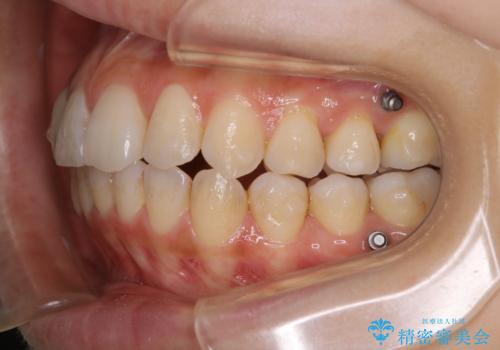

インビザラインの矯正中の方でアタッチメントが歯に付いているため、2ヶ月で着色やプラークが付いてきてしまいました。ホームケアや飲食の仕方により個人差はありますが、基本的には汚れが普段よりもつきやすいです。

定期的にクリーニングすることをおすすめします。